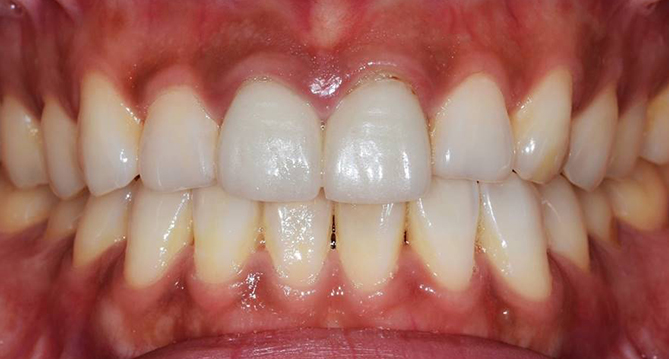

연세새빛치과 전체치아교정[클리피씨] 교정 후